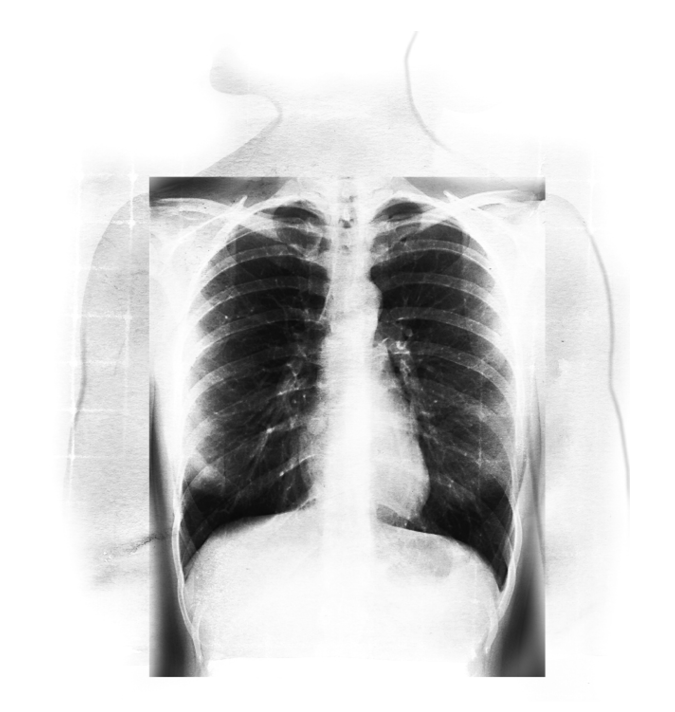

✘误解一:肺脏是个小小的器官,位于身体的中央

谈论肺脏的实际大小、形状、位置之前,我们可以先做做下面的练习:

觉察练习6

把左页的图片影印下来,或是模仿这张图片画出身体的轮廓,然后根据你心里的想法,画出肺脏的形状、大小和位置。

许多人对于肺脏的大小和位置缺乏正确的感知,他们所想的跟事实差距相当远。成人的肺脏大小变化很大,视性别、身高和姿势而定。

多数人身上的肺脏长度介于二十五至三十五公分之间,最宽的地方大约有十至十五公分。肺脏的形状像是切掉顶部的椭圆形,类似橄榄球的形状,不过比橄榄球小一些、窄一些,重量一般是○.九至一.四公斤重。

在左页的X光片中,你可以看到两侧肺脏的实际大小和位置。你所画的图跟这张X光片比起来,有没有什么不同呢?

肺脏的顶部延伸到锁骨上方,当你吸气吸到饱的时候,肺脏的底部几乎会延伸到肋骨的下缘。

觉察练习6的解答

肺脏在身体内的实际大小和位置